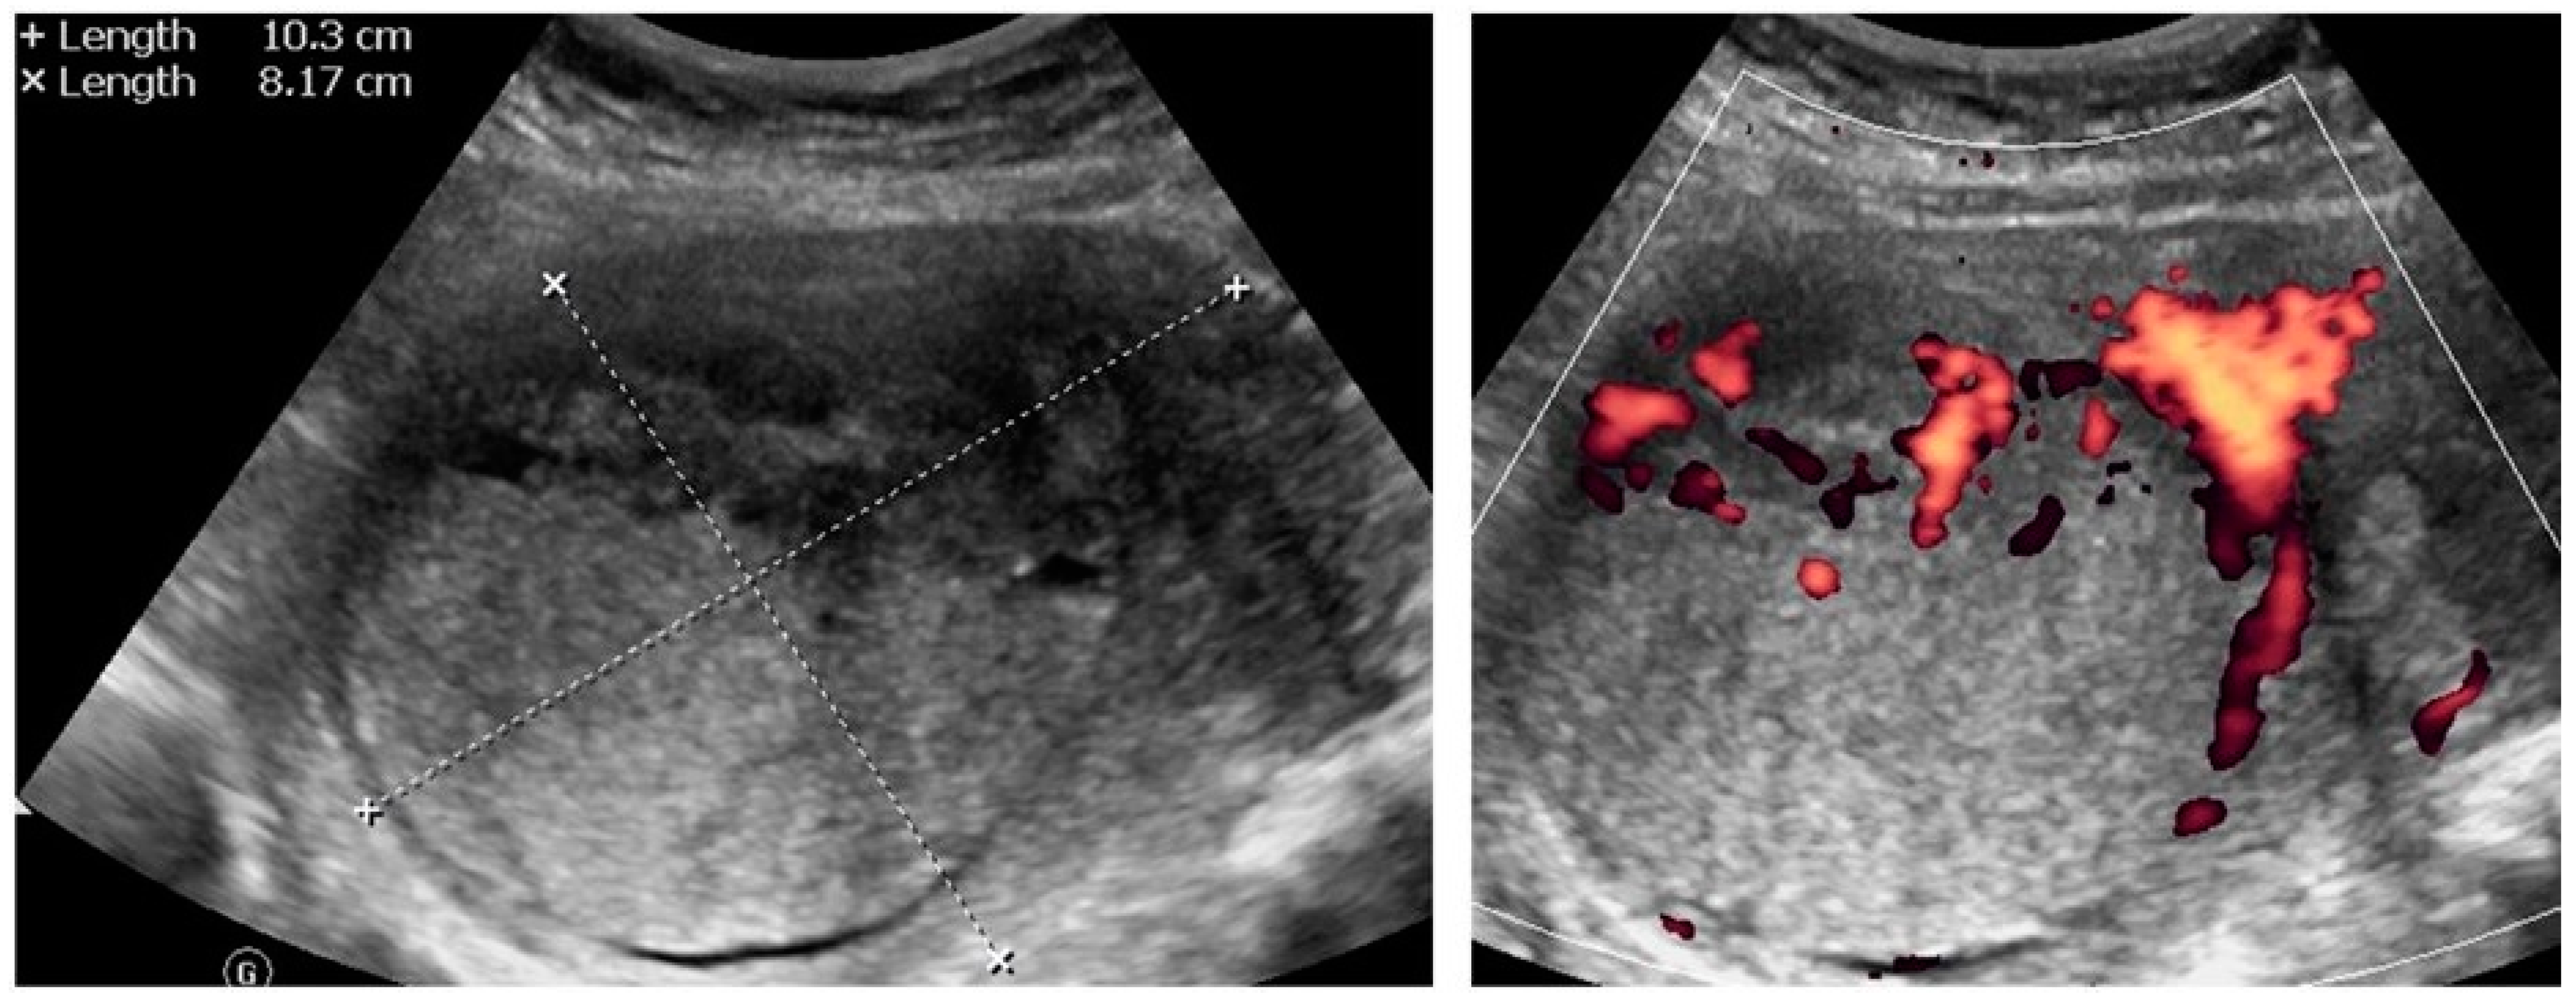

| 1 (44) | Typical uterine lesion (myoma) | Figure A1 | No | Yes | Leiomyoma, cellular variant (UG-TUC core needle biopsy) | Yes (lesion enlarged during follow-up) | Leiomyoma, cellular variant | No | Yes |

| 2 (36) | Sarcoma suspicion | Figure A2 | Yes | Tumorectomy, uterus preservation (young age) | LMS (UG-TUC core needle biopsy) | Yes | LMS | No | Yes |

| 3 (37) | Atypical uterine lesion | Figure A3 | Yes | No | Lipoleiomyoma (UG-TUC core needle biopsy) | No | - | Yes | Yes |

| 4 (56) | Atypical uterine lesion | Figure A4 | Yes | Yes | Leiomyoma (transvaginal ultrasound guided core needle biopsy) | Yes | Leiomyoma and adenomyosis | Yes | No |

| 5 (50) | Atypical uterine lesion (metastatic adenocarcinoma G3 in inguinal lymph node) | Figure A5 | Yes | No | Leiomyoma (UG-TUC core needle biopsy) | No | Uterus / tumor not resected because primary urological carcinoma was diagnosed | Yes | Yes |

| 6 (38) | Atypical uterine lesion | Figure A6 | Yes | No | Leiomyoma, epithelioid variant (UG-TUC core needle biopsy) | Yes (lesion enlarged during follow-up) | Leiomyoma, epithelioid variant | Yes | Yes |

| 7 (29) | Atypical uterine lesion | Figure A7 | Yes | Yes | Leiomyoma (UG-TUC core needle biopsy) | Yes | Leiomyoma with signs of degenerations | Yes | Yes |

| 8 (52) | Atypical uterine lesion | Figure A8 | Yes | Yes | Total abdominal hysterectomy performed without core need biopsy, because of patients age and lesion ultrasound pattern recognition. Note: frozen section result: leiomyoma | Yes | STUMP | - | - |